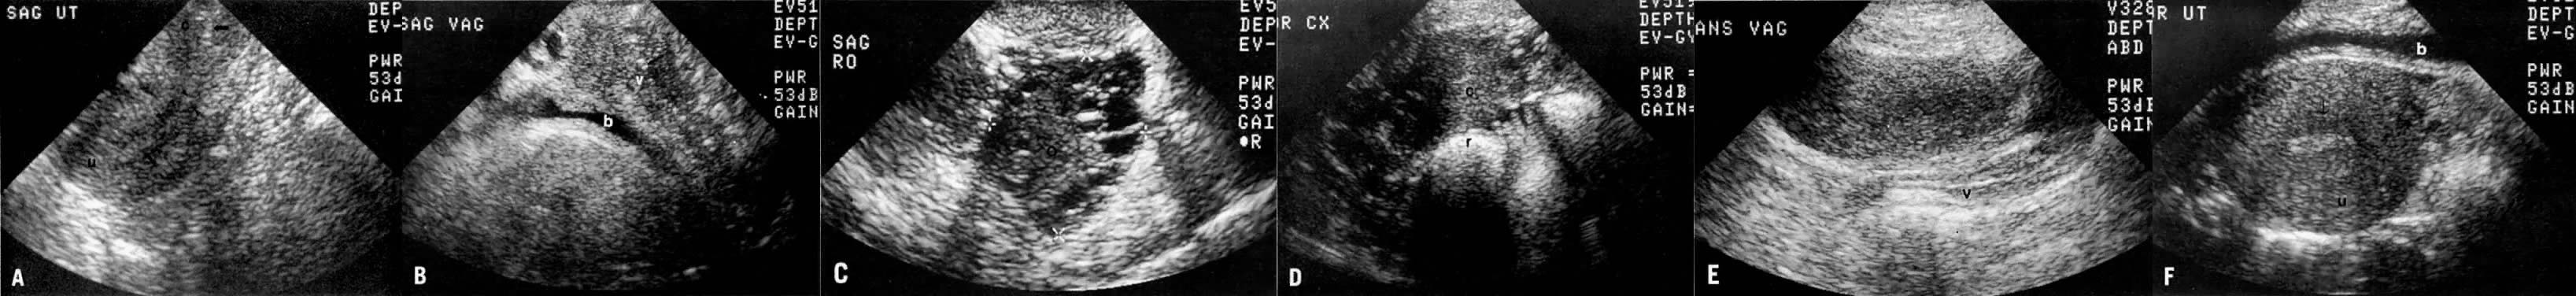

On transvaginal ultrasound (TVUS), the cervix is seen as a medium-echogenicity, 3- to 4-cm long, 3-cm thick cylindrical structure. Two layers can be identified in the cervix: the hyperechoic cervical canal and the medium-echogenicity stroma (Fig. 3A and Fig. 1D). Neither of these layers varies markedly in appearance or thickness during the menstrual cycle. Two distinct layers are seen in the vagina on TVUS: an inner hyperechoic zone, which represents the epithelium and mucous glands; and an outer hypoechoic zone, which represents the muscular wall (Fig. 3B and Fig. 1E).

Fig. 3. TVUS image of a normal pelvis. Sagittal views of the uterus and cervix ( A ), vagina ( B ), and ovary ( C ); and coronal views of the cervix ( D ), vagina ( E ), and uterus ( F ). ( u, uterus; c, cervix; v, vagina; b, bladder; r, rectum; o, ovary; arrows, endometrial stripe and cervical and vaginal canals and mucosae; arrowheads, uterine junctional zone.)

On ultrasound, the uterus is seen as a medium-echogenicity, pear-shaped structure with a central hyperechoic zone, called an endometrial stripe (see Fig. 3A and F). The thickness of this stripe and its echo pattern vary during the menstrual cycle. In the early proliferative phase, it appears as a thin, 2- to 5-mm echogenic stripe. In the late proliferative phase, it has a multilayered appearance: a central hyperechoic line representing the endometrial cavity, and subjacent isoechoic and hyperechoic layers representing the endometrium and its glands. In the late secretory phase, the endometrial stripe appears uniformly hyperechoic and fairly thick (up to 15 mm). Frequently seen subjacent to the endometrial stripe is a hypoechoic junctional zone that is somewhat thinner than the junctional zone seen by MRI. The outer thick medium-echogenicity zone represents the outer myometrium. In postmenopausal women, the endometrial stripe decreases in thickness and should not exceed 5 mm. Similarly, the myometrium decreases in thickness with considerable decrease in the size of the uterus.